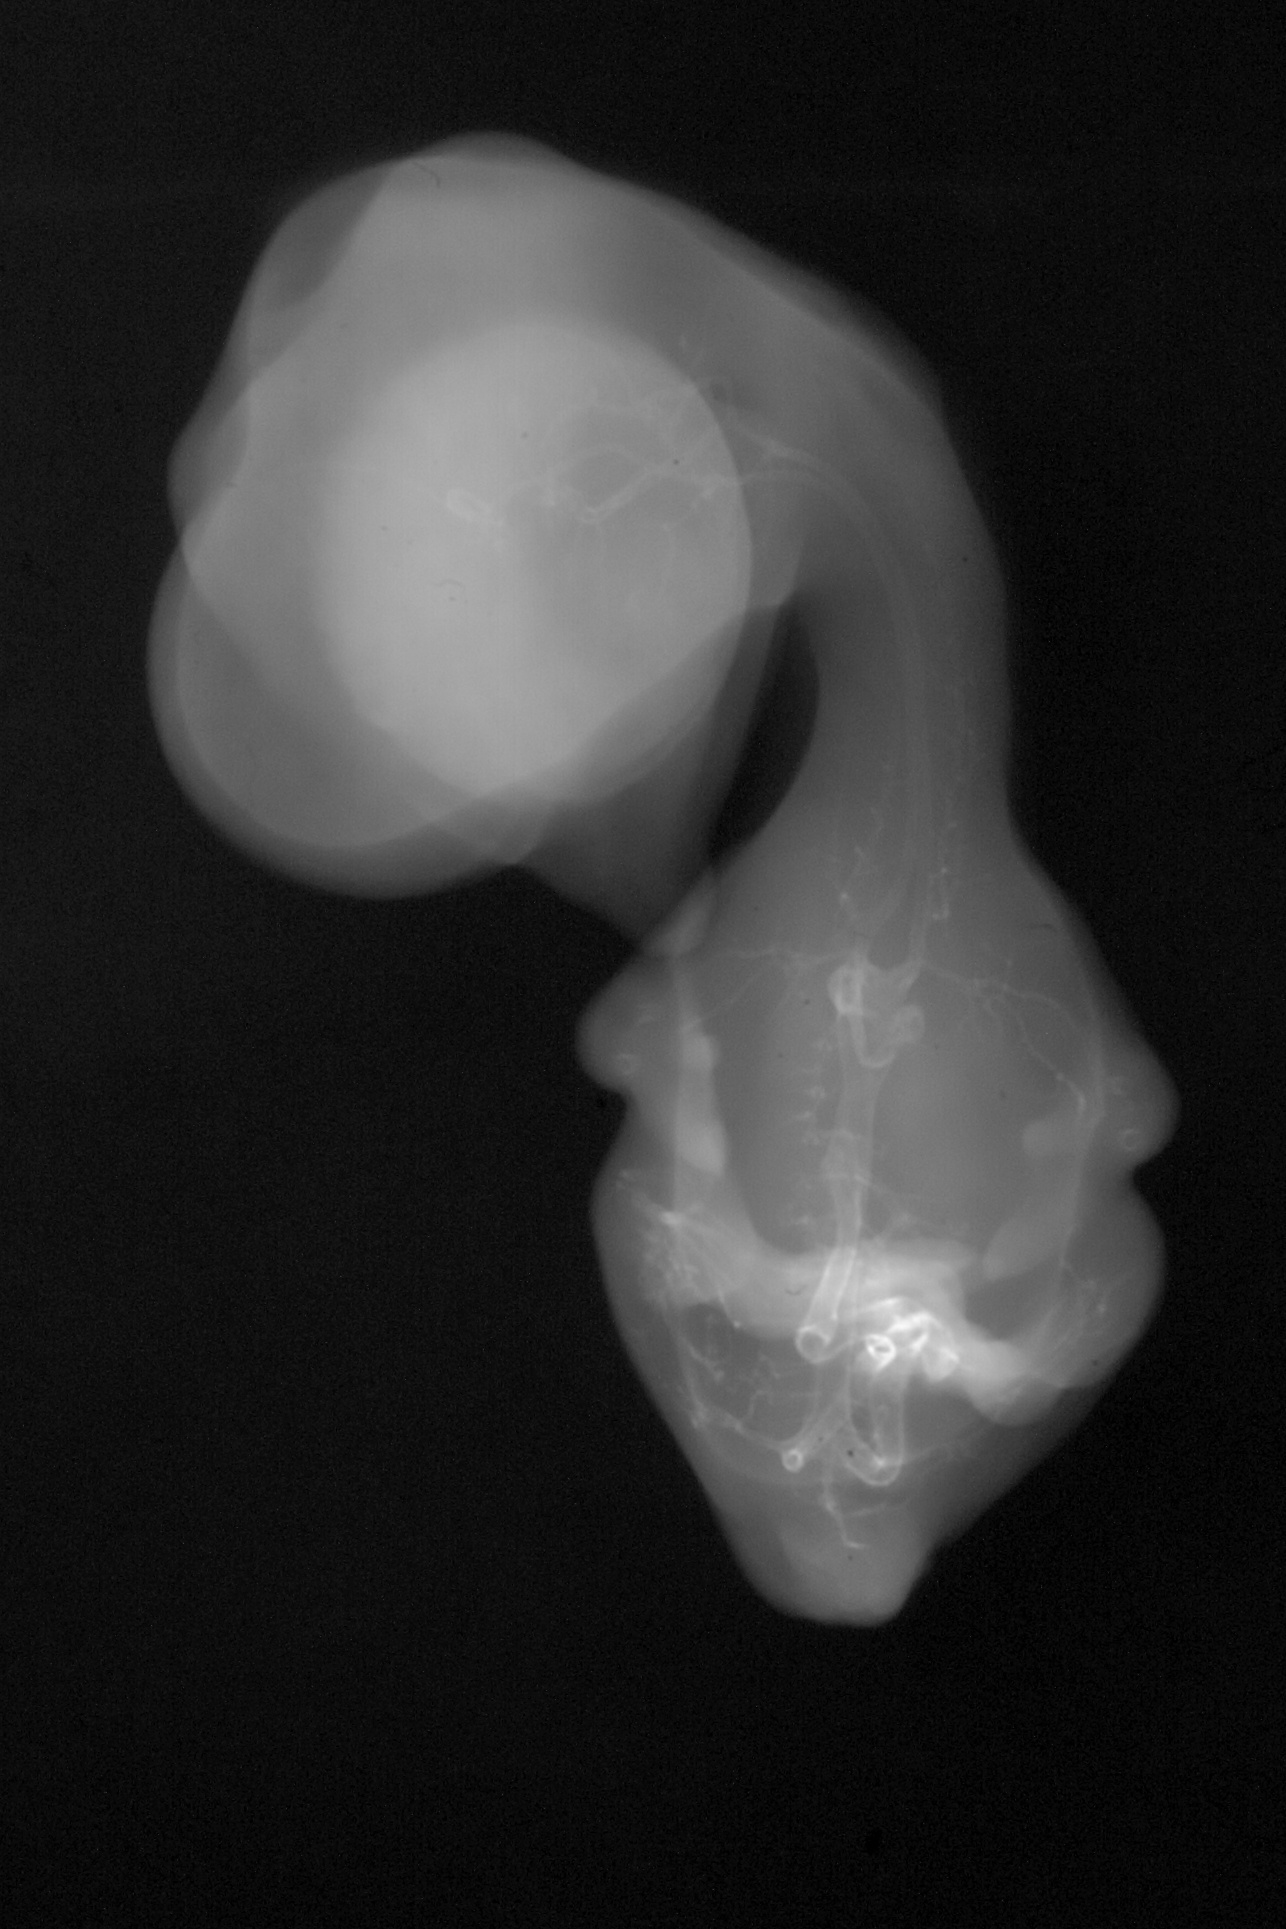

Chick Embryo Microangiography

Hamburger-Hamilton (HH) Stage 35 (approx. 8.5 - 9 days)

X-Ray Micrographs